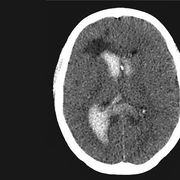

脑动脉瘤是颅内动脉血管的异常瘤状突起。脑动脉瘤不破裂,一般病人没有明显症状,如果破裂出血,常表现为蛛网膜下腔出血,病人可以出现剧烈的头痛,恶心呕吐,甚至出现...11216人收听

- 数字减影血管造影技术,颅内动脉瘤介入治疗,湘雅护理学院,颅内动脉瘤,颅内动脉瘤系指脑动脉壁的异常膨出部分,是引起自发性蛛网膜下腔出血的最常见原因。病因-尚不甚清楚,但以先天性动脉瘤占大部分。任何年龄可

- 颅内动脉瘤介入治疗的护理,主讲人杨鑫,。,一、概述颅内动脉瘤时由于局部血管异常改变产生的脑血管样突起。其主要症状多由出血引起,部分因瘤提压迫,动脉痉挛及栓塞造成。,,,,,,,,,,,,二、颅内动脉瘤介入适应症和禁忌症适应症、几乎所有的动脉

- 脑动脉瘤相关知识脑动脉瘤简单说就是脑动脉血管壁上膨出的血管泡,血管泡在血液不间断的冲击下,就象吹气球一样,球吹得越大,血管壁就变得越薄,血管也就越容易破裂。一般认为